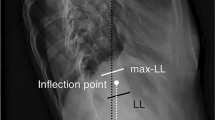

3D shape parameters were automatically calculated using SterEOS software [12, 13] (EOS-Imaging). Four 3D parameters were defined (Fig. 1):

Illustration of the four transverse plane parameters. The axial apical vertebral rotation (AVR) corresponds to the rotation of the axial apical vertebra in the reference coordinate system (EOS system). The intervertebral axial rotations correspond to the angle of axial rotation between the end vertebrae of the curve and the adjacent vertebrae at lower and upper junctions. The torsion index is the mean of the two sums of intervertebral axial rotations from lower junction to the apex, then from the apex to the upper junction

Torsion index: this index, proposed by Steib et al. [9], indicates to what extent vertebrae are continuously rotated with regard to the other from lower neutral vertebra to the apex, and then from the apex to the upper neutral vertebra. The torsion index is the mean of the two sums of intervertebral axial rotations from lower junction to the apex, and then from the apex to the upper junction.